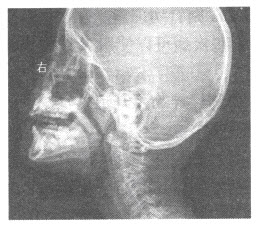

65、单项选择题

女,5岁,耳鸣,常开口呼吸,睡眠时打鼾,鼻腔分泌物多。X线检查如图所示,最可能的诊断是()

A.鼻息肉

B.扁桃体炎

C.腺样体肥大

D.鼻炎

E.鼻窦炎